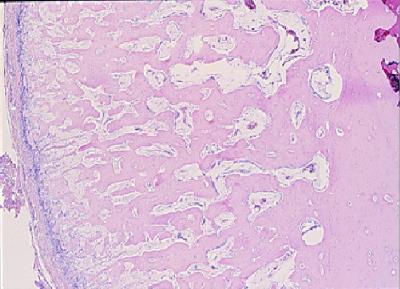

图片左侧纵向排列,细胞密集的膜性结构为骨膜,骨膜下有大量的新生骨骼组织。